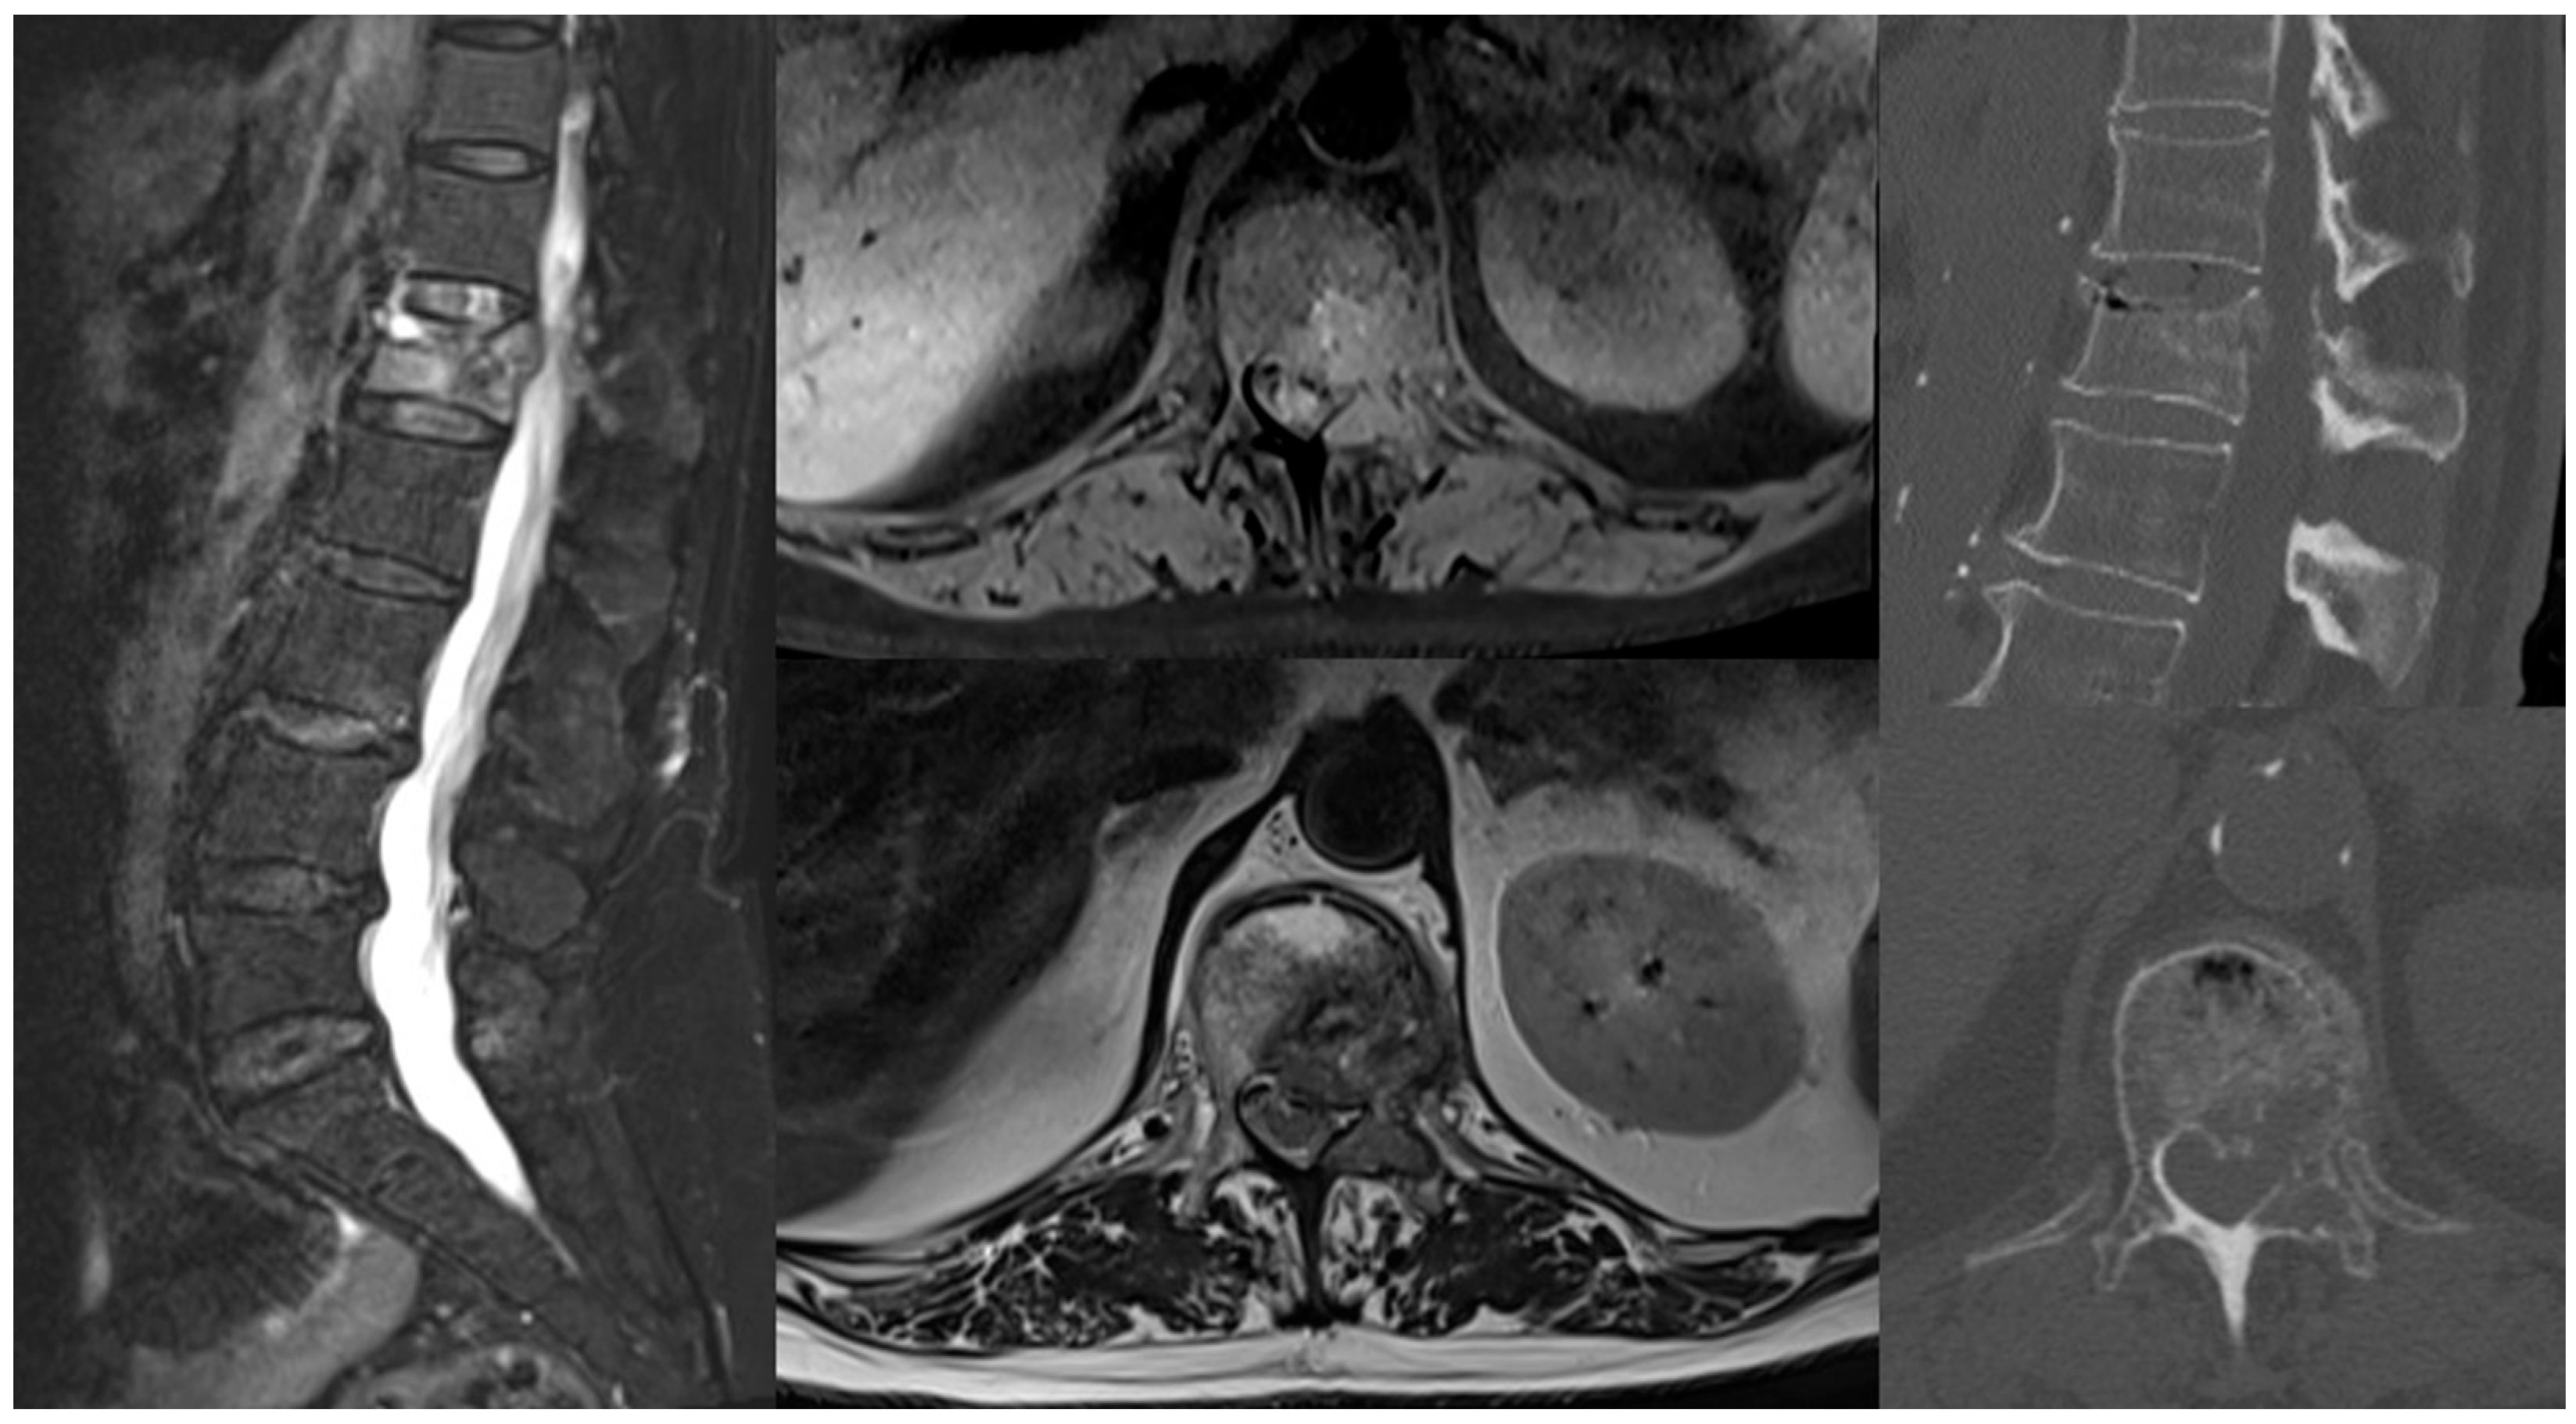

2.1. History and Presentation

2.2. Pre-Operative Planning and Treatment Strategy